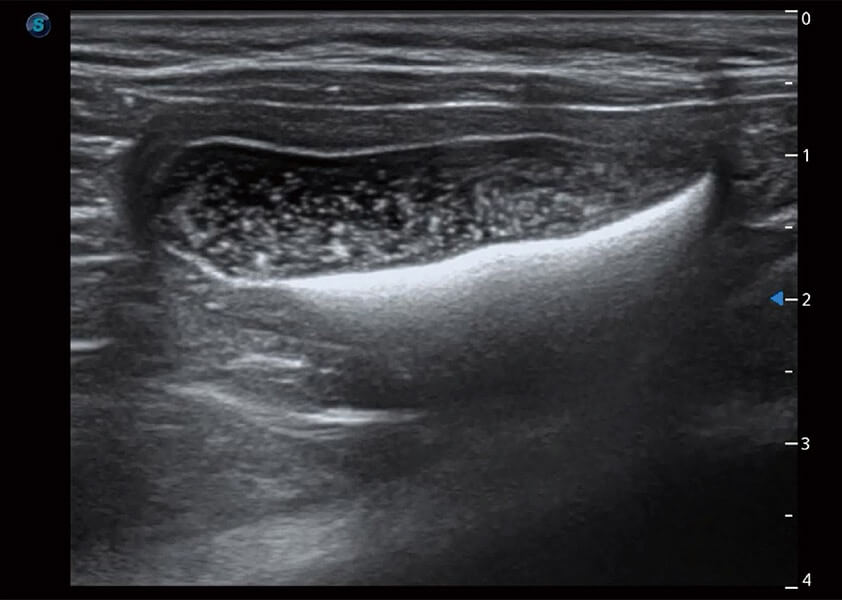

ProPet 60 作为一款高端台式动物超声设备,为动物医生的日常诊断提供了一系列贴合动物临床需求、解决临床实际问题的高级成像功能。凭借全系列高清探头,满足医生对腹部、心脏、生殖、浅表、肌骨等成像的所有需求,切实帮助您提升检查效率,提高诊断信心。

动物是人类最亲密的朋友和最值得信赖的伙伴。环球UG官网也一直致力于探索动物专用的超声影像解决方案。 全新推出的ProPet系列,是环球UG官网在动物超声影像智能化、专业化、精准化的一次跨越式革新。动物不能用言语来表述自己的不适,通过超声影像,ProPet系列搭建了动物医生与不同物种沟通的“桥梁”,为动物医生注入了“治愈之力”。